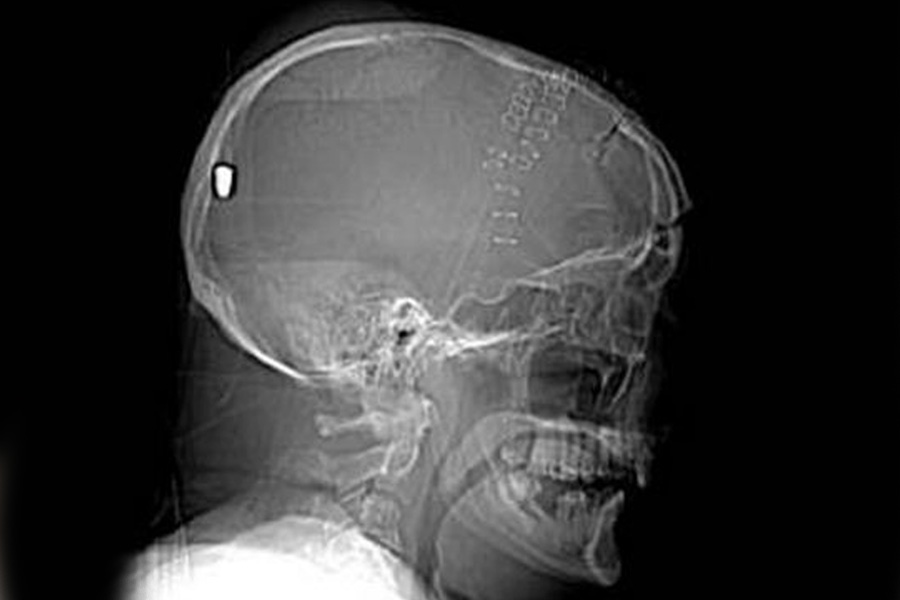

ঘুম থেকে উঠে দেখেন, মাথায় অসম্ভব যন্ত্রণা। প্রথমে বুঝে উঠতে পারেননি কেন এ রকম হচ্ছে। চিকিৎসকের কাছে ছোটেন তরুণ। গিয়ে যা জানতে পারেন, তাতে তিনি হতবাক। তাঁর মাথায় নাকি আটকে রয়েছে আস্ত বুলেট! তার পরেও দিব্যি বেঁচে রয়েছেন তিনি। কে মেরেছে গুলি? তরুণ মনে করতে পারেননি। যদিও শেষ পর্যন্ত অভিযুক্তের হাজতবাস হয়েছে।

পরে অস্ত্রোপচার করে মাইকেলের মাথা থেকে বুলেট বার করেন চিকিৎসকেরা। মাইকেল সেরে গেলেও ভেঙে পড়েন মাইকেলের স্ত্রী এপ্রিল।

কিন্তু মাইকেল এ সব টের পাননি কেন? আদৌ কি সত্যি কথা বলছেন যুগল? চিকিৎসকদের দাবি, কোনও কিছুতে লেগে ছিটকে গুলি ঢোকে মাইকেলের মাথায়। ফলে তার অভিঘাত ছিল অনেক কম। তাই বরাতজোরে বেঁচে যান তিনি।

কিন্তু তিনি কিছুই টের পেলেন না কী ভাবে? চিকিৎসকদের একাংশের মতে, গুলি লেগে সম্ভবত অজ্ঞান হয়ে যান মাইকেল। ঘুম থেকে উঠে মাথা যন্ত্রণা হওয়ার যে তত্ত্ব তিনি দিচ্ছেন, তা হয়তো তাঁর জ্ঞান ফেরার পর, ঘুম ভাঙার নয়। বুলেটের অভিঘাতে তাঁর স্মৃতির একাংশ লোপ পেয়েছিল বলেও মনে করেন অনেকে। তবে সে দিন ঠিক কী ঘটেছিল, সেই প্রশ্নের উত্তর আজও মেলেনি।